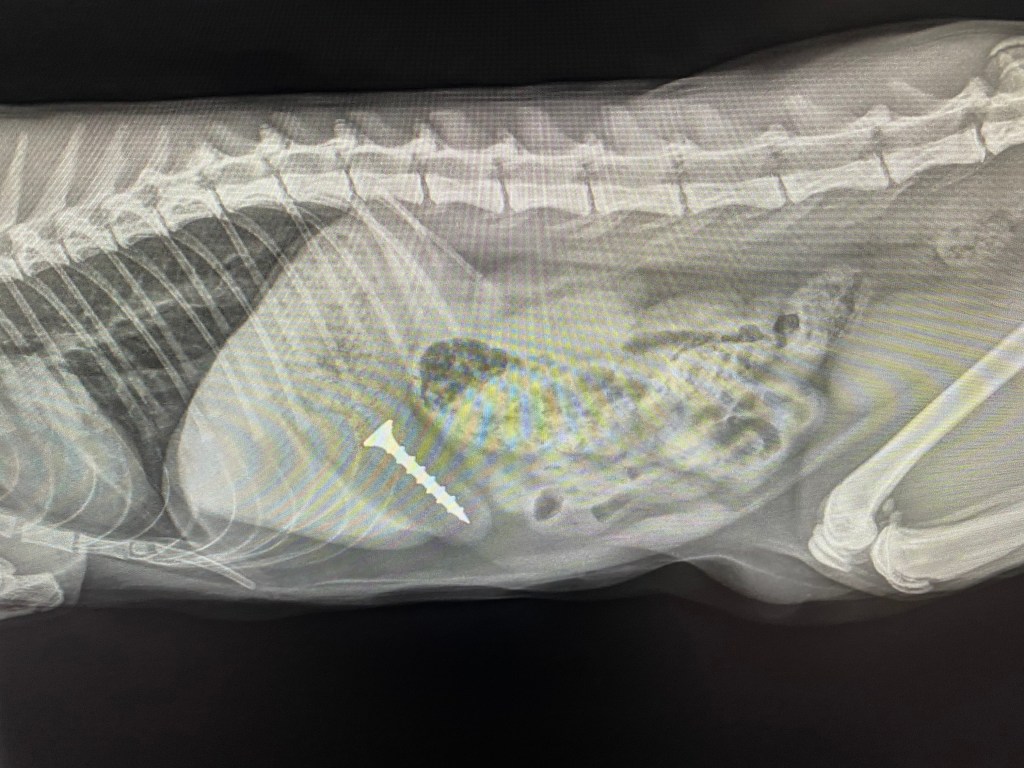

The next patient has also traveled more than 200 km to us – a cat with a “loose screw”…..to be precise one that has unmistakably lodged itself in the stomach and here an emetic is not having the desired effect.

At least it is a very rewarding surgical case and half an hour later there is the unmistakable plinging of a metal object being dropped into a kidney dish. Another half an hour later and the cat is sitting upright in its cage asking for food and the screw has been washed and returned to the owner in pristine condition for the next DIY project.